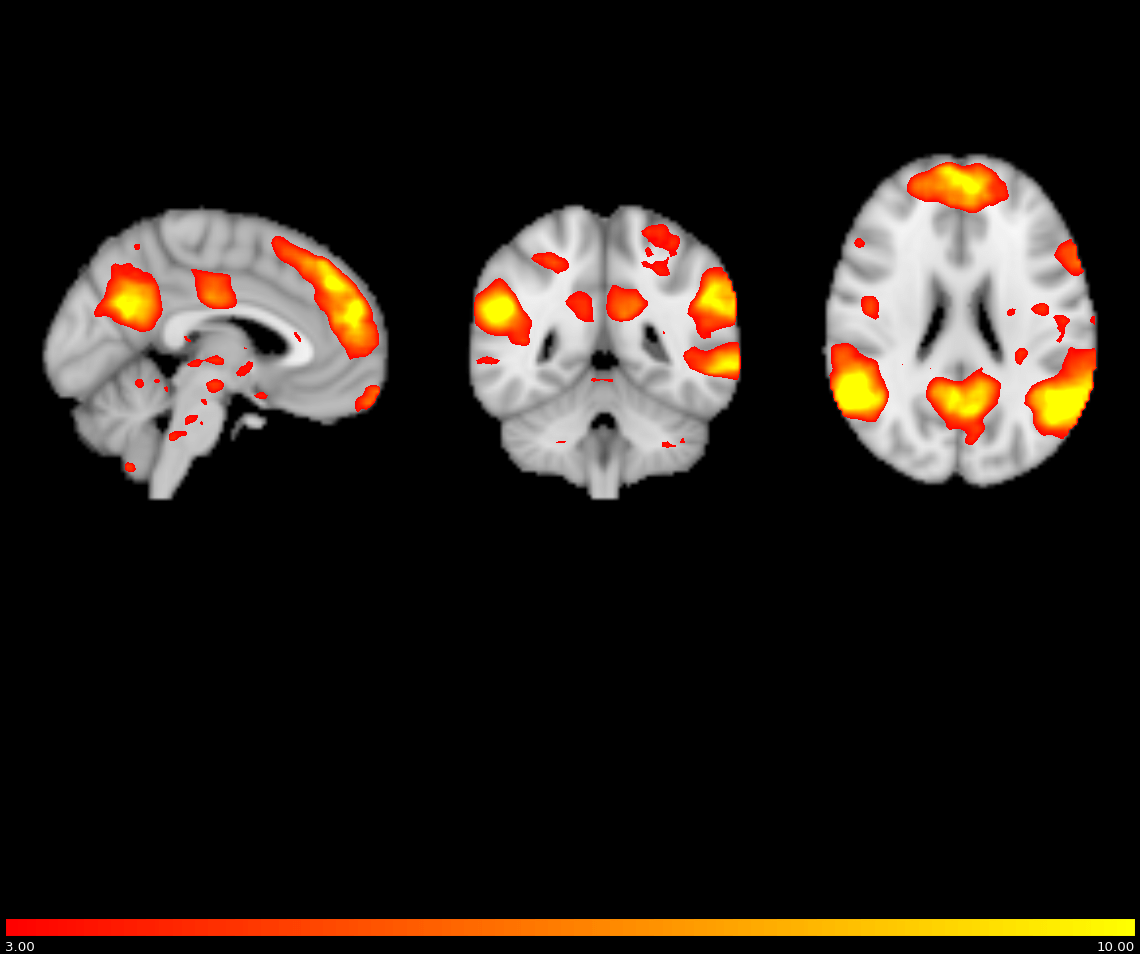

Differences in Resting State Brain Networks and Cognition in Familial Adenomatous Polyposis (Current)